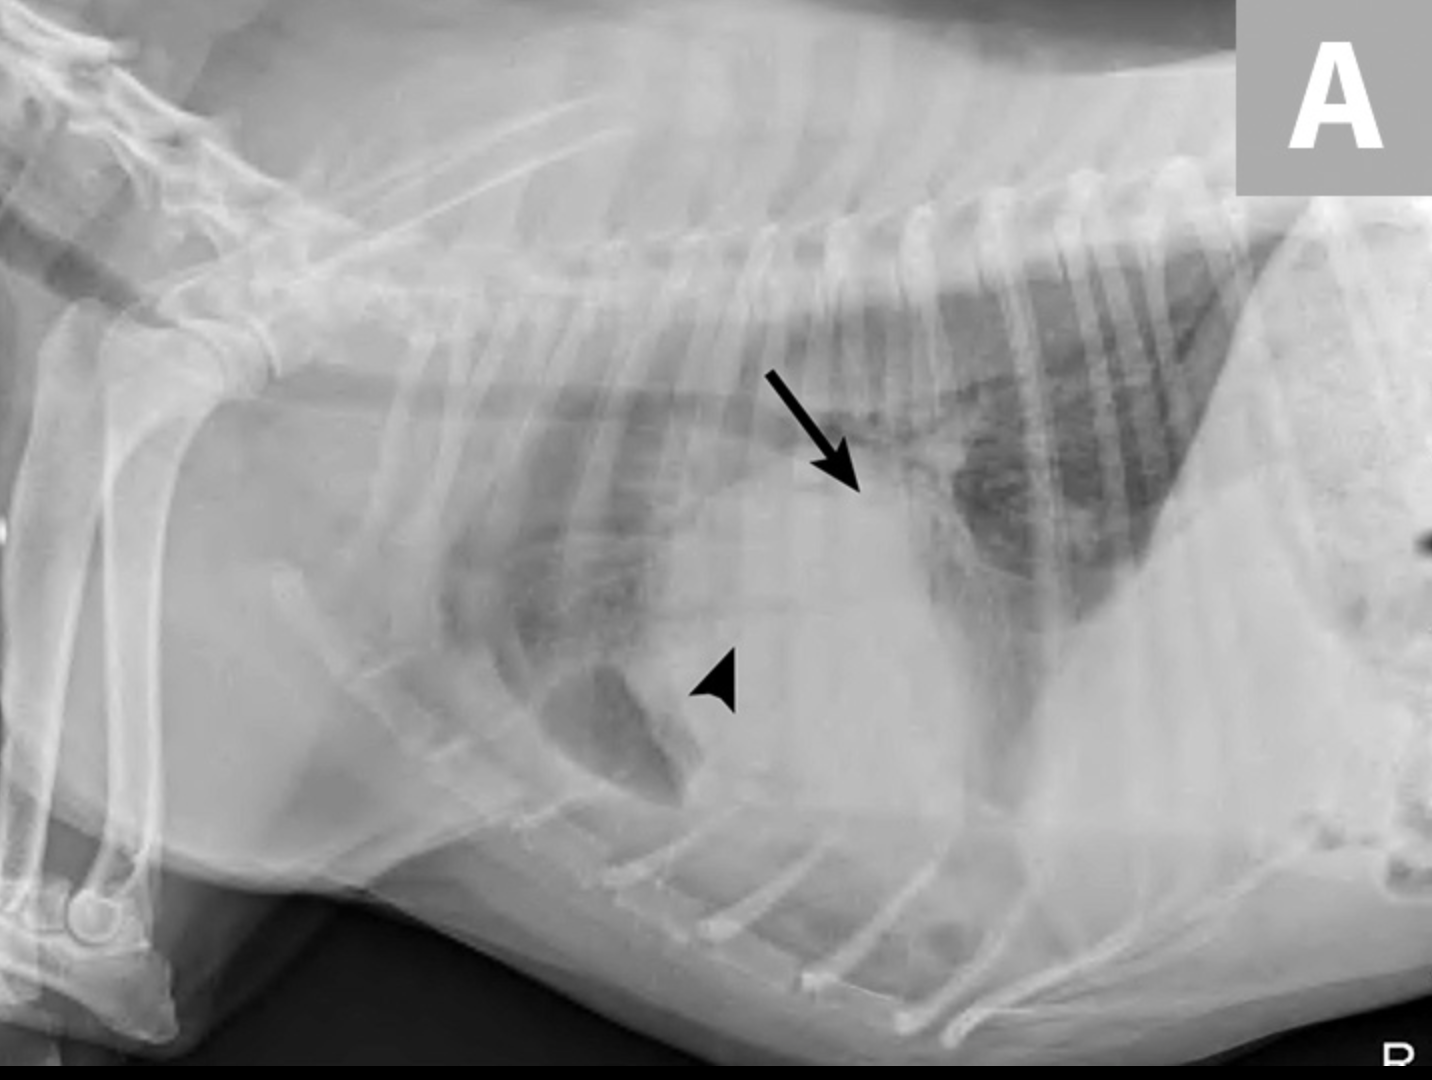

Las radiografías obtenidas después de la toracocentesis demostraron un derrame pleural mejorado y la consolidación del lóbulo medio izquierdo del pulmón (Figura 3). Basado en el abultamiento de los tejidos blandos cerca del hilio y el broncoramón de aire que se extiende cranealmente, el diferencial primario fue la torsión del lóbulo pulmonar (LLT). Otras consideraciones incluyen masa pulmonar, absceso o granuloma.